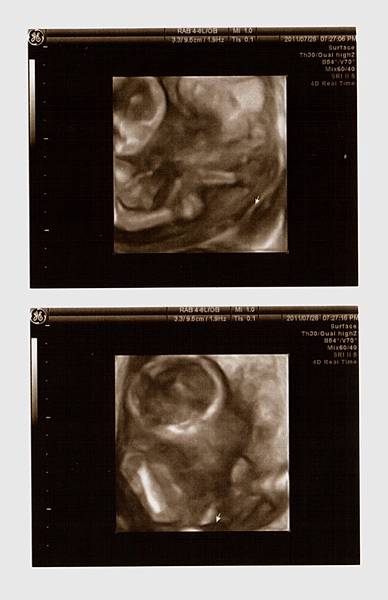

接著,重頭戲來囉,黃醫師幫我照了超音波,躺在床上的我和站在一旁的老公顯得緊張,當我還在思考等一下醫生會告訴我寶寶究竟是男是女之際,思路還來不及轉彎之時,黃醫師就已迅雷不及掩耳的速度告訴我:『這是男寶寶喔!』我驚訝的不得了!還說『怎麼看啊?在哪在哪?』醫生不急不徐地說:『這是寶寶的弟弟,有看到凸出來的,那就是弟弟喔!』天啊,是弟弟啊(說實在,我真想看看老公當時的表情><)接著,醫師告訴我寶寶的頭偏大,看來是個大頭弟,大腿骨普通長(媽媽我還以為他是個長腿男勒!),然後醫師拿著探頭四處看,告訴我寶寶的一切都正常,讓媽咪我放心了許多!

一連串拿了七張超音波照片,還看了4D的超音波,真是超棒的唷!!!